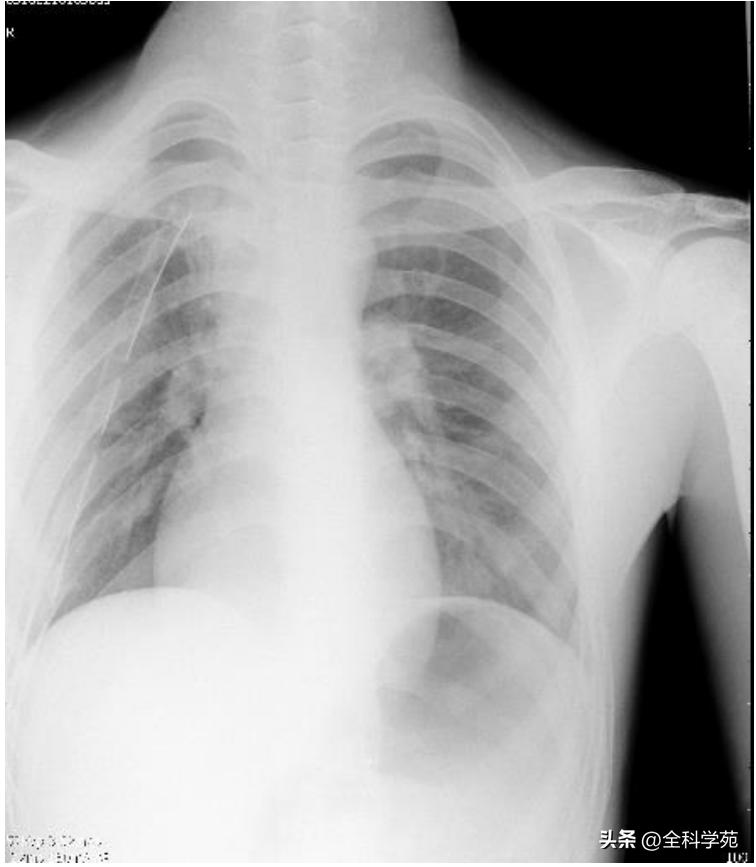

胸片: 胸腔闭式引流状态,右侧气胸较前消失

行胸腔闭式引流术抽出积气后,复测心电图可见 肢体导联振幅较前明显增高